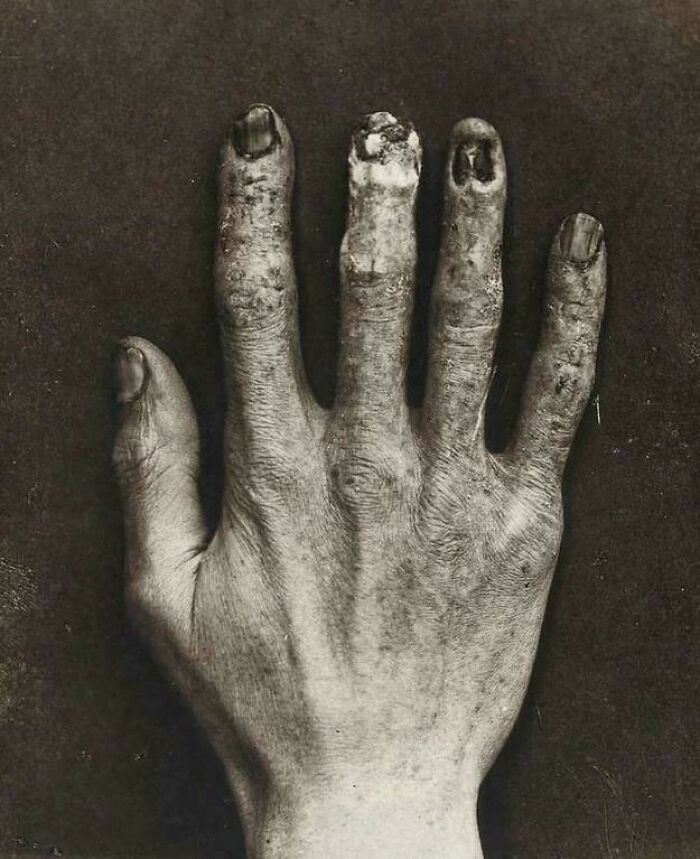

Radiation Damage From Back in the Early 1900s—The X-Ray Tech’s Hand Says It All